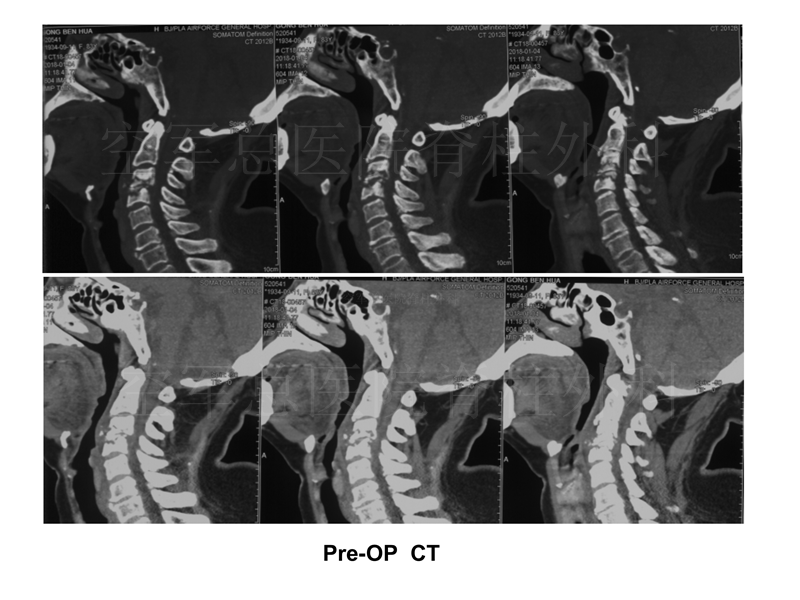

影像检查:

现病史:颈肩部疼痛7月,双上肢麻木2月,四肢无力,大小便障碍1月,无发热、盗汗、乏力等症状

既往史:高血压50年,房颤10余年,房颤射频消融术后6年,脑梗30年,后遗右下肢活动障碍;否认结核、牛羊等接触病史

查体:颈3-4棘突压痛(+);双上肢、胸2以下、双下肢、会阴区感觉减退,右侧为著;双上肢肌力0-I级,双下肢肌力II-III级;双上肢腱反射活跃,双下肢腱反射减弱;Hoffmann(-),巴氏征(+),髌、踝阵挛(-);JOA评分1分。

实验室检查:WBC:4.9G/L,中性粒细胞:76%;C反应蛋白:24.6mg/L、血沉:45mm;结核杆菌γ干扰素释放试验(+);降钙素原(-);布氏杆菌凝集试验(-);肿瘤全套(-);D二聚体:3420;EF:52%;左室壁节段性运动异常;双下肢动脉硬化伴斑块形成;左侧胸膜局限性增厚、粘连,小气道功能下降。